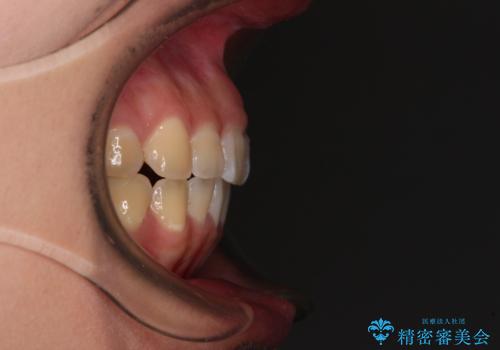

- 上下の前歯が非接触であることと、それに伴う口元の閉じにくさを気にして来院された患者様です。

奥歯の咬み合わせを見ると、上顎が下顎に対して相対的に前方にありました。

口元の閉じにくさを改善するためには、上顎臼歯を後方に移動させた咬み合わせにする必要があります。

インビザライン単体で改善することも可能ですが、達成する可能性が高くないため、カリエールディスタライザーという補助装置を併用して、より確実性を上げることとしました。

奥歯の咬み合わせを改善しながら、並行してインビザラインで歯列を整えることとしました。

カリエールディスタライザーを併用したことで、確実かつ短期間で治療を終えることができました。